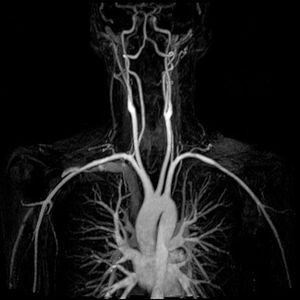

This is a truly unique test that views our body's remarkable complexity in such a simplistic way. The MRA uses magnetic field, radio waves and a computer to evaluate blood vessels and help identify abnormalities or detect aneurysms, dissections, ruptured and atherosclerotic disease of the aorta and all its branches. Unlike traditional angiography that involves placing a tube (catheter) into the body, MRA is noninvasive and requires contrast in order to visualize the blood vessels. Notice the heart along with the aorta, aortic arch, and its 3 main branches (brachiocephalic trunk, left common carotid artery, and left subclavian artery).